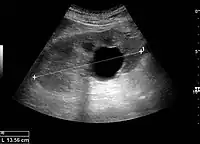

Complex cysts can have membranes dividing the fluid-filled center with internal echoes, calcifications or irregular thickened walls. The complex cyst can be further evaluated with Doppler US, and for Bosniak classification and follow-up of complex cysts, either contrast-enhanced ultrasound (CEUS) or contrast CT is used (Figure 6). The Bosniak classification is divided into four groups going from I, corresponding to a simple cyst, to IV, corresponding to a cyst with solid parts and an 85–100% risk of malignancy.[1] In polycystic kidney disease, multiple cysts of varying size in close contact with each other are seen filling virtually the entire renal region. In advanced stages of this disease, the kidneys are enlarged with a lack of corticomedullary differentiation (Figure 7).[1]

Figure 6. Complex cyst with thickened walls and membranes in the lower pole of an adult kidney. Measurements of kidney length and the complex cyst on the US image are illustrated by '+' and dashed lines.[1]